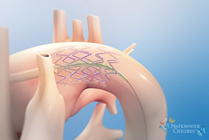

Pediatric Cataracts